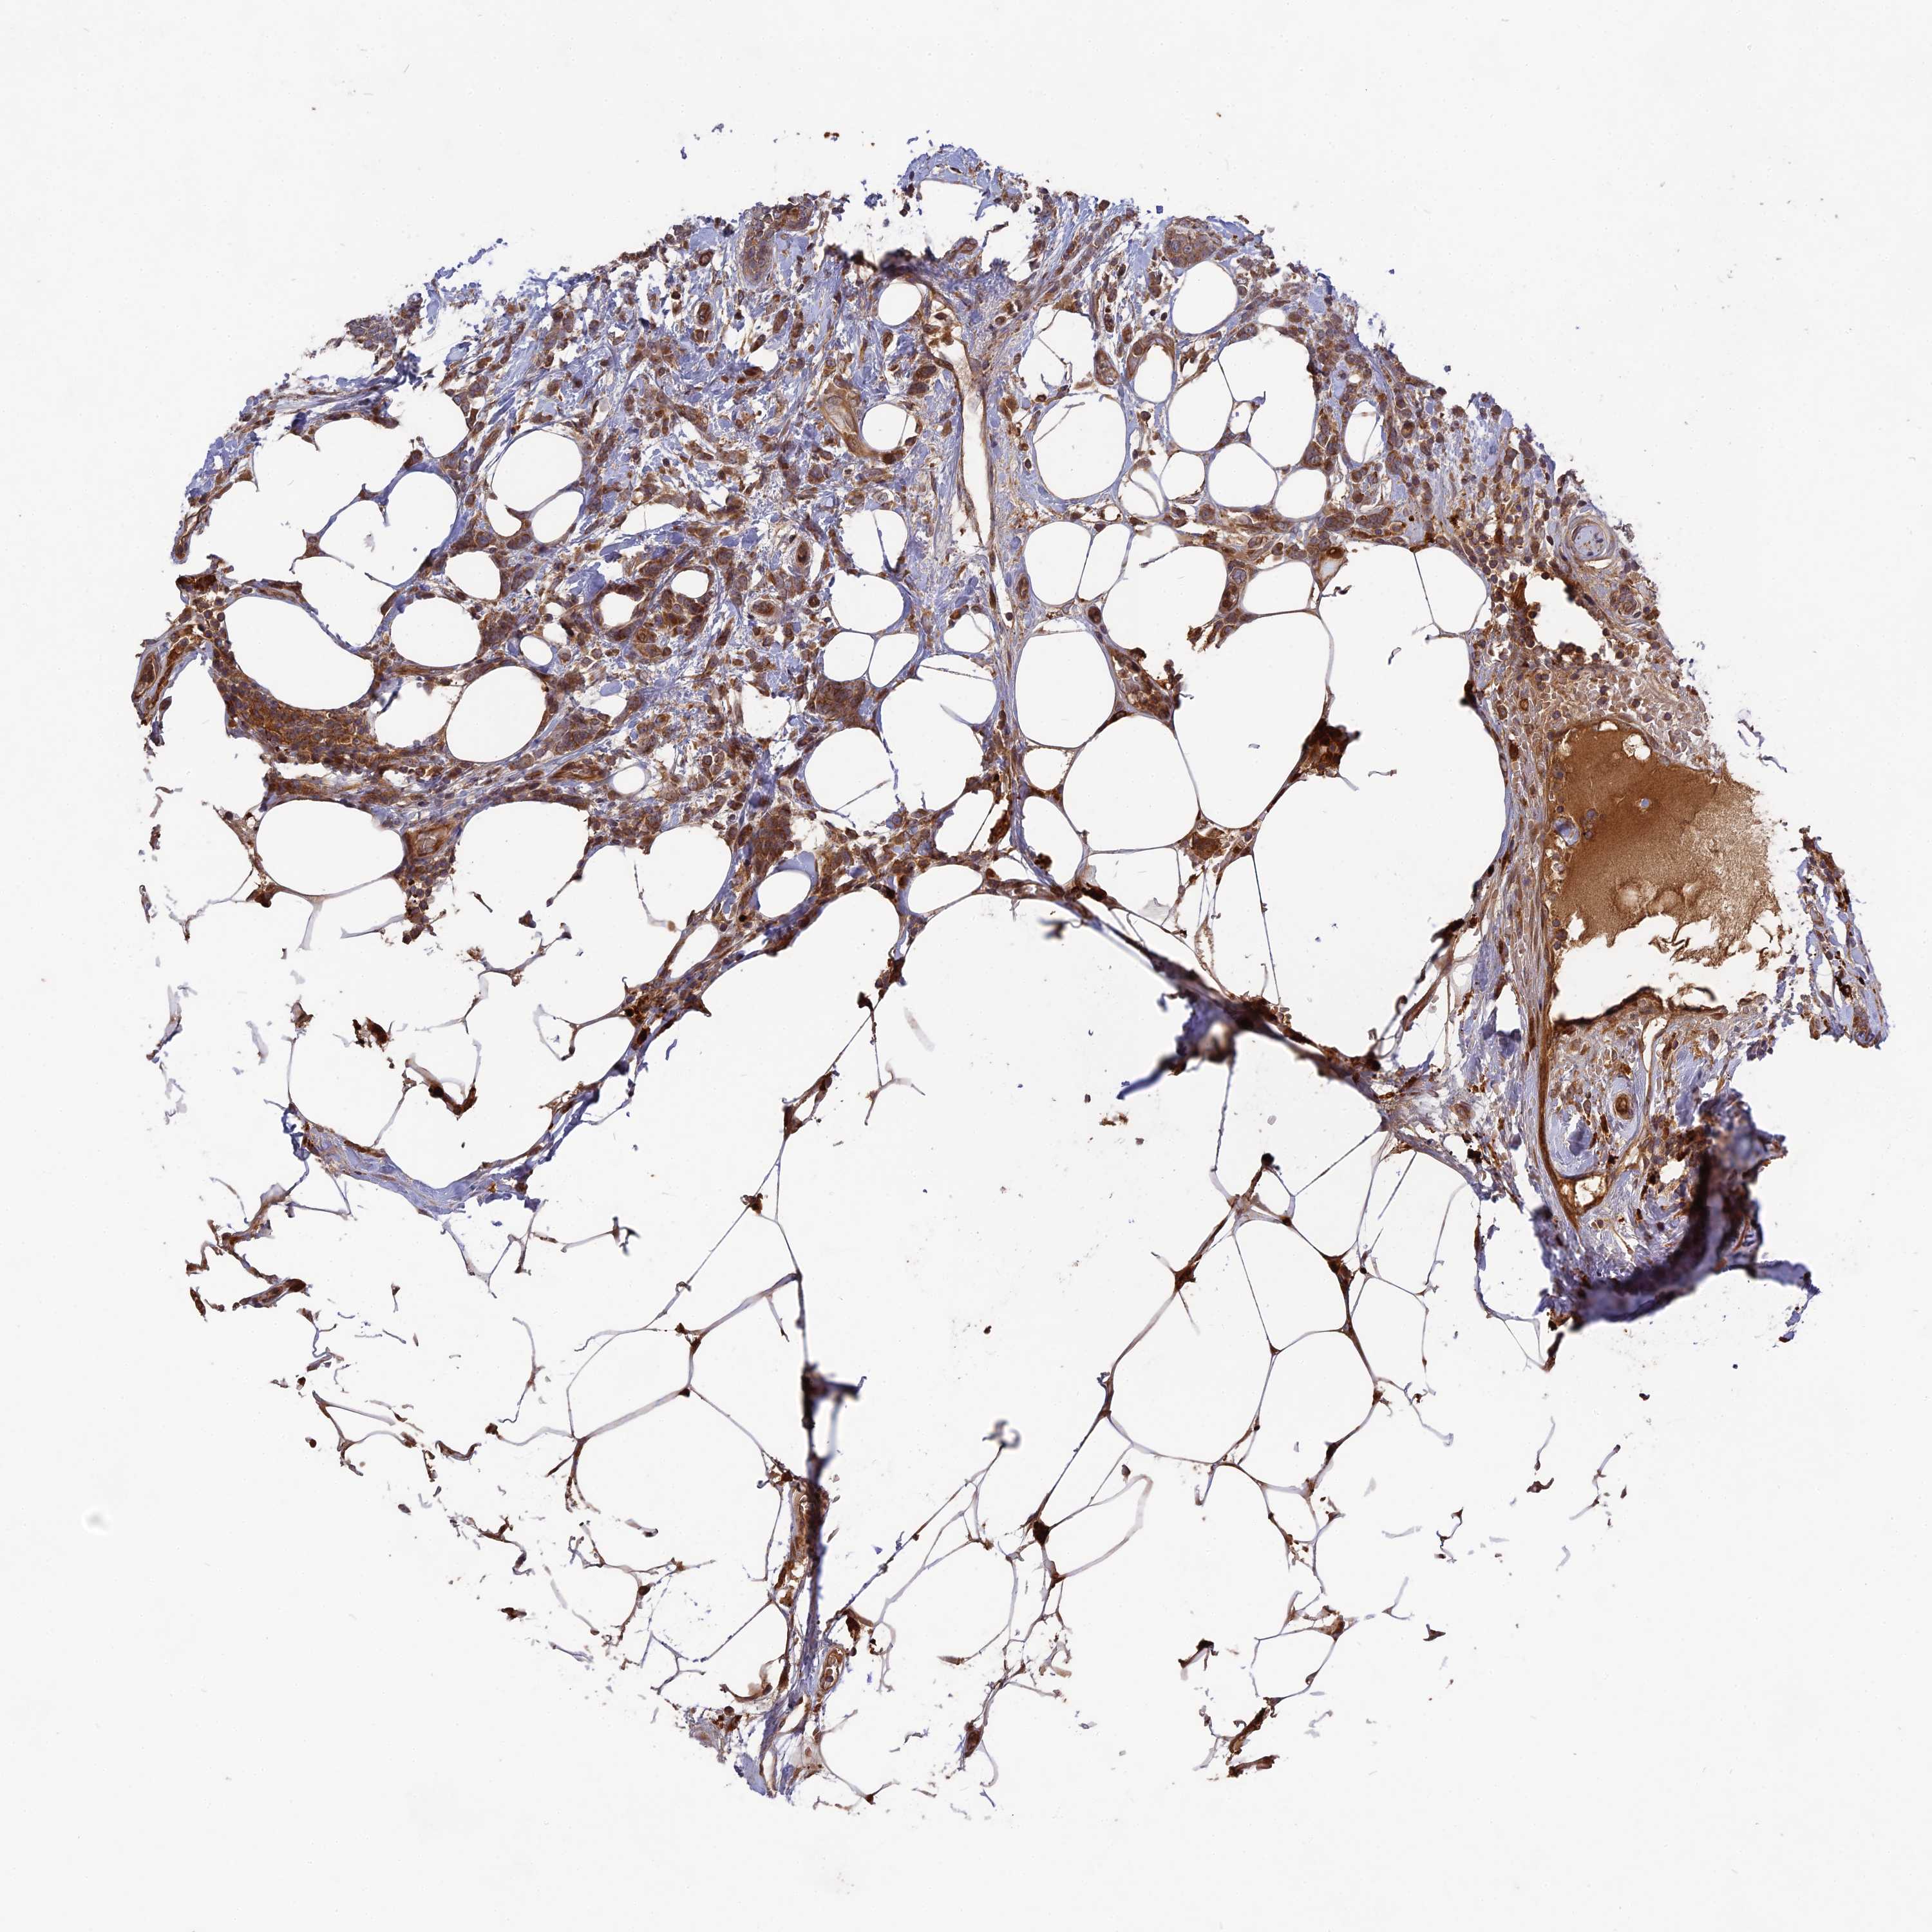

BRCA TCGA BRCA VALIDATION PROTEIN EXPRESSION

ANTIBODIES

AND

VALIDATION